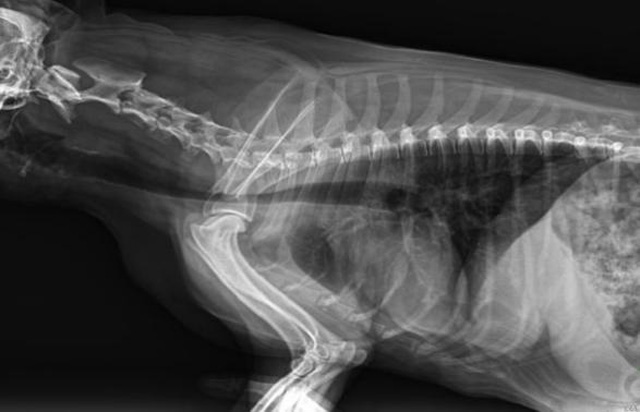

從臨床角度出發,大力發展動態DR,以精準的診斷為小動物保駕護航。寵物DR升級使用雙焦點球管,大尺寸平板探測器,超高頻逆變高壓發生器。醫用纖維板臺面,防止寵物劃傷。寵物DR整機小巧實用,骨略結構和器官位置,分類詳細,運算更快,讓拍攝條件更科學,有助于提高診斷的準確性和效率。安裝移動非常方便。低輸入電流設計,220伏常規電壓。多品種動物程序設定,滿足各個臨床需求。成像效果顯著,寵物不能言語表達,導致誤診率居高不下。寵物診療均以經驗診斷為主的方式,確保最小化輻射降低對醫生及動物的影響。以滿足精細化的寵物醫療需求,成為診斷寵物內外科疾病的必備工具。使醫院更有競爭力,為醫院創收增光添彩。

寵物DR的操作流程是什么呢?第一步首先插上整機電源,然后按下主機電源。打開高壓發生器的電源,工作站主機電源。等待主機軟件的自動啟動。通過軟件登記檢查的寵物信息,選擇寵物檢查拍攝部位。調節限速器拍攝區域。關閉鉛房門,點擊開始拍攝按鈕。拍攝完成調整圖像并且輸出。